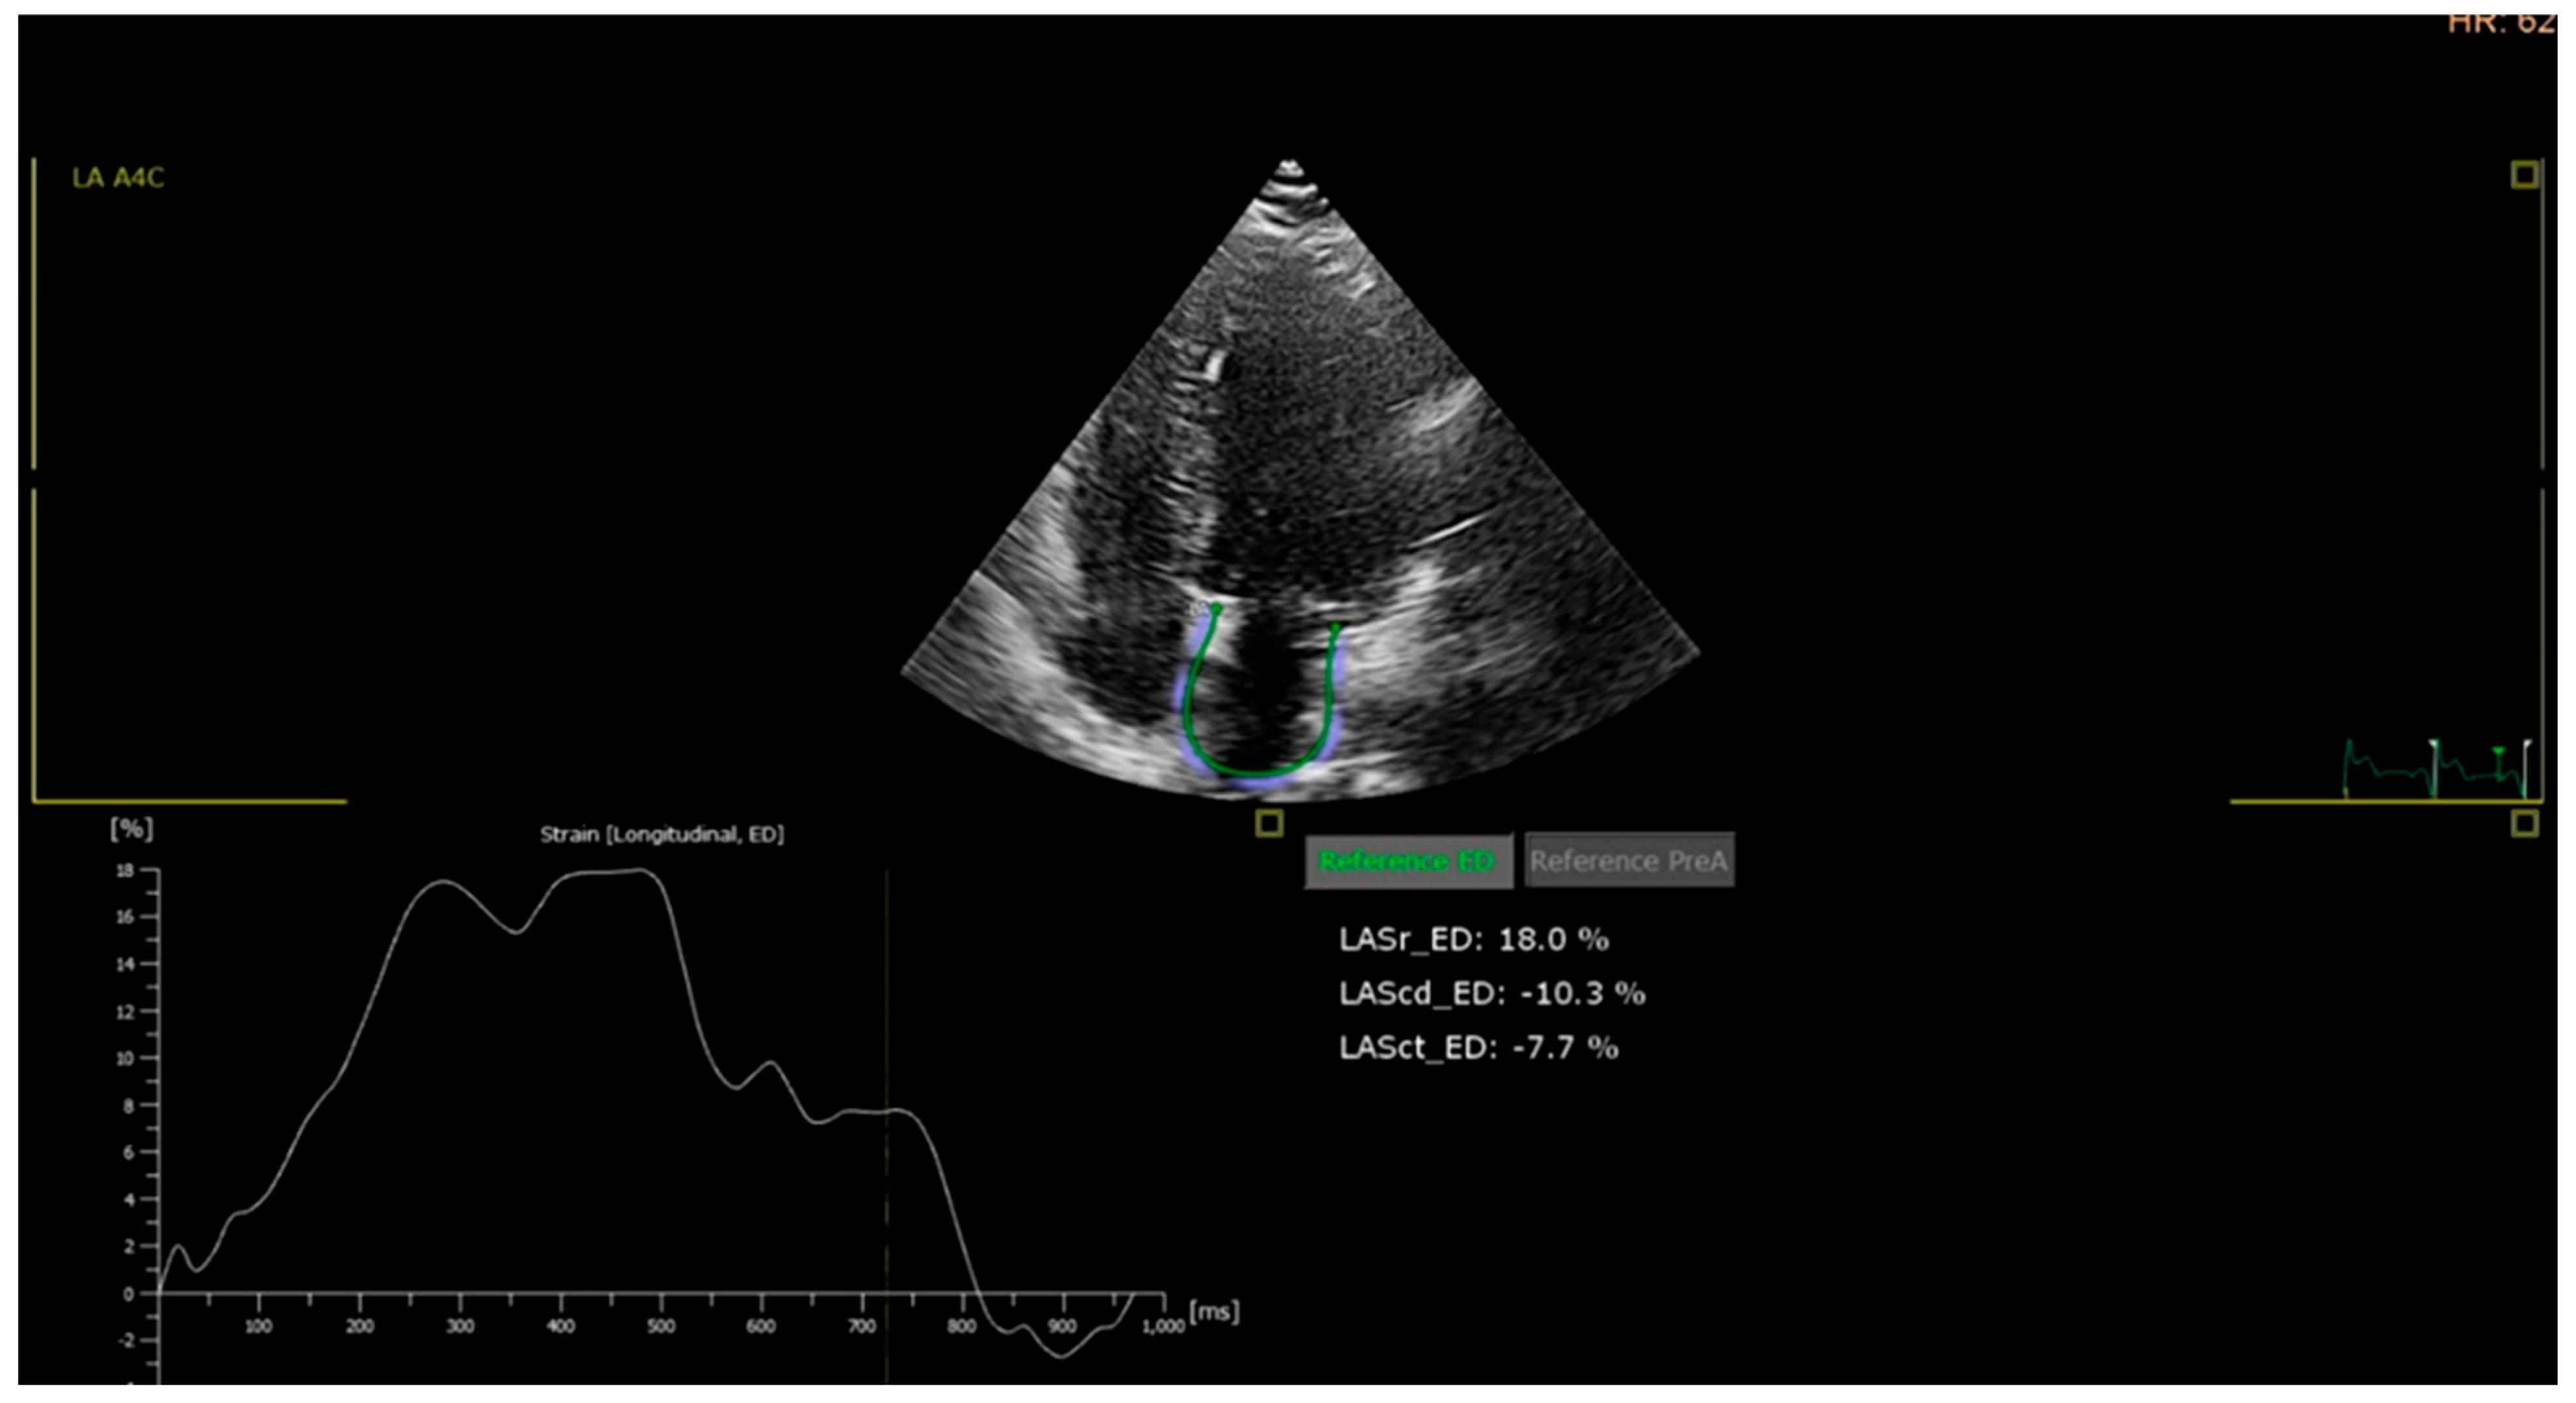

- Left atrial (LA) strain: LA reservoir strain was measured using speckle-tracking from apical four-chamber views focused on the left atrium. A value below 35% was considered abnormal, based on the lower limit of the 95% confidence interval observed in the control group and supported by literature data.

| LA strain, % | 42 ± 6 | 38 ± 7 | 34 ± 8 | 32 ± 8 | <0.001 |

| Abnormal LA strain (<35%), n (%) | 6 (10.0) | 24 (30.0) | 48 (60.0) | 52 (65.0) | <0.001 |